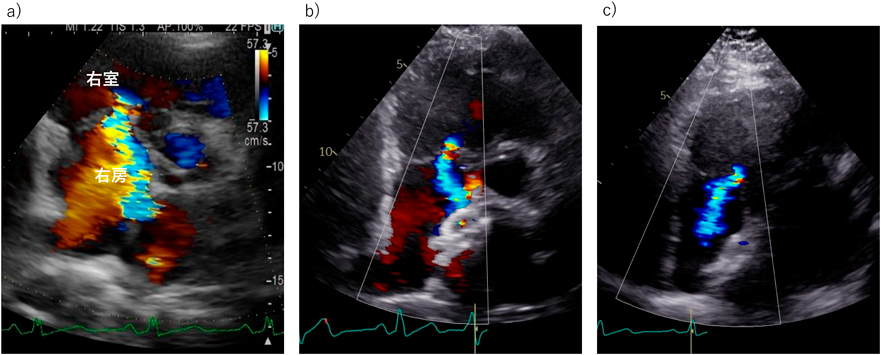

Fig. 2 三尖弁逆流と僧帽弁逆流を合併した79歳ASD患者の心エコー

a)術前には著明な右房,右室拡大,左房拡大を認め,重度三尖弁逆流,中等度僧帽弁逆流を認めた.b)外科的ASD閉鎖+三尖弁形成術+僧帽弁形成術+左心耳閉鎖術後を施行.2年後には弁逆流は制御されており,右心系は縮小した.

Fig. 3 70歳男性の経カテーテル心房中隔欠損症閉鎖術前後での三尖弁逆流の変化

a)心房中隔欠損症閉鎖術前では右心系の拡大に伴う三尖弁輪の拡大と重度の三尖弁逆流を認めた.b)カテーテル閉鎖後2か月ですでに三尖弁逆流は軽度まで改善している.c)カテーテル閉鎖後1年でも三尖弁逆流ごく軽度にとどまっている.